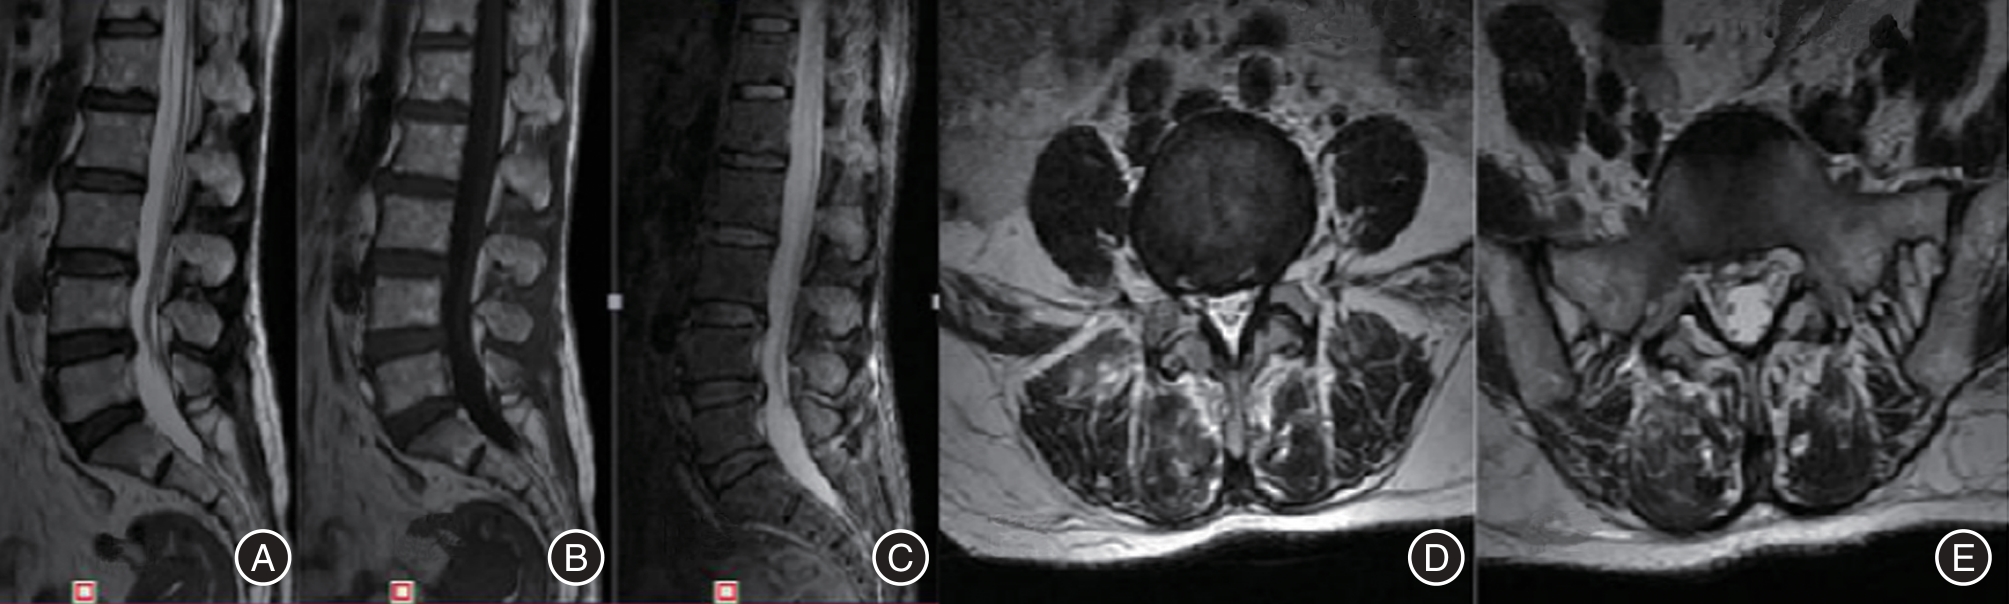

目的 探讨单一切口椎间孔镜治疗双节段腰椎管狭窄并腰椎间盘突出症的临床疗效。 方法 回顾性分析2016年3月至2018年5月在广西中医药大学第一附属医院脊柱骨伤科就诊的40例双节段腰椎管狭窄并腰椎间盘突出症患者临床资料,其中通过单一切口同时穿刺椎间孔镜治疗的患者11例(A组),通过单一切口前后穿刺椎间孔镜治疗的患者13例(B组),通过双切口前后穿刺椎间孔镜治疗的患者16例(C组)。记录患者的一般临床资料,三组不同时间点(术前、术后即刻、术后1周、术后1个月、末期随访)的VAS评分、JOA评分及临床疗效,并运用统计学进行分析。 结果 三组间手术时间、术中透视次数、皮肤切开长度和满意度差异均有统计学意义(P < 0.05);手术时间与手术方式在VAS、JOA评分上存在交互作用;手术时间、手术方式在VAS、JOA评分上存在主效应(P < 0.05);三组术后即刻、术后1周、术后1个月、末期随访与术前在VAS、JOA评分上比较差异均有统计学意义(P < 0.05);三组间术后即刻在VAS、JOA评分上差异有统计学意义(P < 0.05);三组间术后1周在VAS评分上差异有统计意义(P < 0.05)。 结论 单一切口椎间孔镜技术同时减压双节段腰椎管狭窄并腰椎间盘突出症的有效手段,具有手术时间短、术中透视少,损伤小等优势,患者满意,值得临床推广应用。

Objective To evaluate the clinical effectiveness of single?incision intervertebral foraminotomy in treating double?segment lumbar spinal stenosis accompanied by lumbar disc herniation. Methods A retrospective analysis was conducted on 40 cases of double?segment lumbar spinal stenosis and lumbar disc herniation treated in our orthopedic (spinal surgery) department from March 2016 to May 2018. Among these cases, 11 patients (Group A) were treated with percutaneous discectomy, 13 patients (Group B) underwent percutaneous endoscopic discectomy, and 16 patients (Group C) received double?incision percutaneous surgery. General clinical data for all patients were recorded. Visual Analog Scale (VAS) scores, Japanese Orthopaedic Association (JOA) scores, and clinical outcomes were assessed at five different time points: preoperatively, immediately postoperatively, one week postoperatively, one month postoperatively, and at the final follow?up. Statistical analysis was performed on the collected data. Results The operation time, the number of fluoroscopies performed on the hands, the length of the skin incision, and patient satisfaction were all statistically significant (P < 0.05). An interaction effect was observed between the operation time and the surgical procedure on both the VAS and JOA scores. Both the operation time and the surgical method had significant main effects on the VAS and JOA scores (P < 0.05). Significant differences in VAS and JOA scores were found among the three groups immediately post?surgery, one week post?surgery, one month post?operation, and at the end of the study (P < 0.05). Immediately after surgery, there were statistically significant differences in VAS and JOA scores among the three groups (P < 0.05). One week post?surgery, there were also statistically significant differences in VAS scores among the three groups (P < 0.05). Conclusions The single?incision intervertebral foramen technique is an effective approach for simultaneously addressing double?segment lumbar spinal stenosis and lumbar disc herniation through decompression. This method boasts a shorter operative duration, reduced intraoperative radiation exposure, and minimal tissue damage. Patient satisfaction is high, making it a valuable addition to clinical practice.